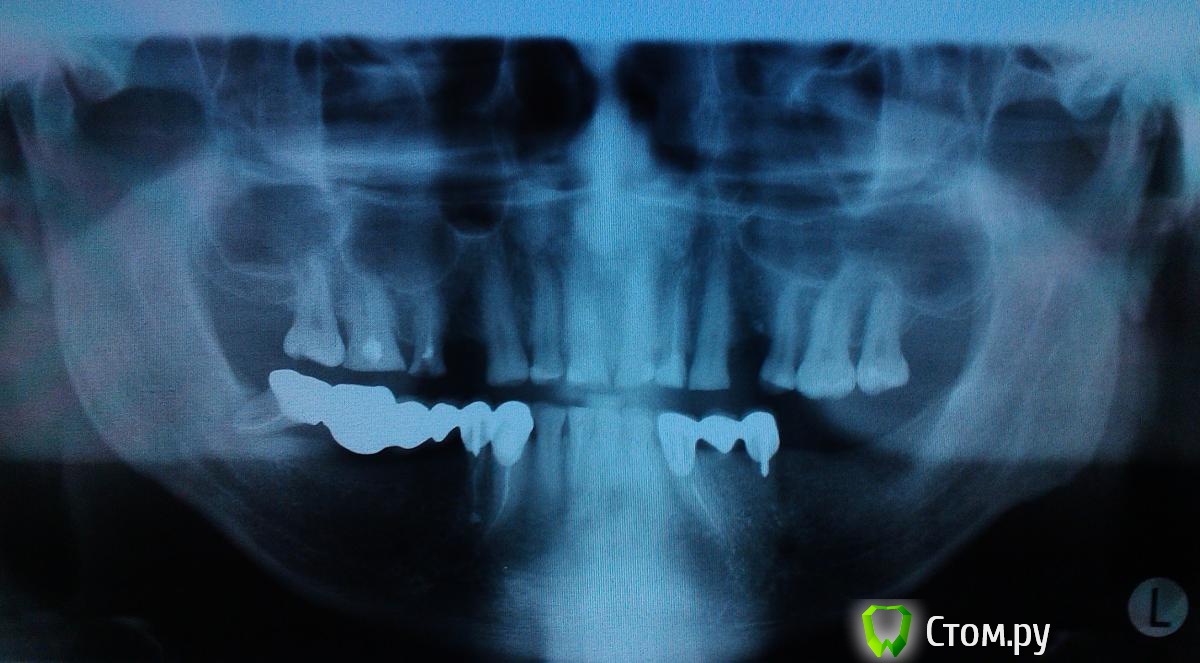

Rival Опубликовано 21 мая, 2014 Автор Поделиться Опубликовано 21 мая, 2014 (изменено) Сделайте и выкладывайте панорамный снимок http://forum.stom.ru/topic/2813-obiazatelno-k-prochteniiu/сделал снимок Изменено 21 мая, 2014 пользователем Rival Ссылка на комментарий

red_butler Опубликовано 21 мая, 2014 Поделиться Опубликовано 21 мая, 2014 (изменено) 1. Снять мостовидный протез 4.3 4.4 4.82. Удалить 4.83. Перелечить 1.54. Имплантация 1.4 2.4 3.6 3.7 4.5 4.6 4.75. Протезирование 1.4 1.5 2.4 3.6 3.7 4.5 4.6 4.7 Изменено 21 мая, 2014 пользователем red_butler Ссылка на комментарий